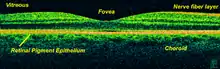

The vertebrate retina has 10 distinct layers.[15] From closest to farthest from the vitreous body:

- Inner limiting membrane – basement membrane elaborated by Müller cells

- Nerve fibre layer – axons of the ganglion cell bodies (a thin layer of Müller cell footplates exists between this layer and the inner limiting membrane)

- Ganglion cell layer – contains nuclei of ganglion cells, the axons of which become the optic nerve fibres, and some displaced amacrine cells[2]

- Inner plexiform layer – contains the synapse between the bipolar cell axons and the dendrites of the ganglion and amacrine cells[2]

- Inner nuclear layer – contains the nuclei and surrounding cell bodies (perikarya) of the amacrine cells, bipolar cells, and horizontal cells[2]

- Outer plexiform layer – projections of rods and cones ending in the rod spherule and cone pedicle, respectively, these make synapses with dendrites of bipolar cells and horizontal cells.[2] In the macular region, this is known as the Fiber layer of Henle.

- Outer nuclear layer – cell bodies of rods and cones

- External limiting membrane – layer that separates the inner segment portions of the photoreceptors from their cell nuclei

- Inner segment / outer segment layer – inner segments and outer segments of rods and cones, the outer segments contain a highly specialized light-sensing apparatus.[16][17]

- Retinal pigment epithelium – single layer of cuboidal epithelial cells (with extrusions not shown in diagram). This layer is closest to the choroid, and provides nourishment and supportive functions to the neural retina, The black pigment melanin in the pigment layer prevents light reflection throughout the globe of the eyeball; this is extremely important for clear vision.[18][19][20]

Layers imagable with optical coherence tomography

Using optical coherence tomography (OCT), 18 layers can be identified in the retina. The layers and anatomical correlation are:[24][25][26]

From innermost to outermost, the layers identifiable by OCT are as follows: